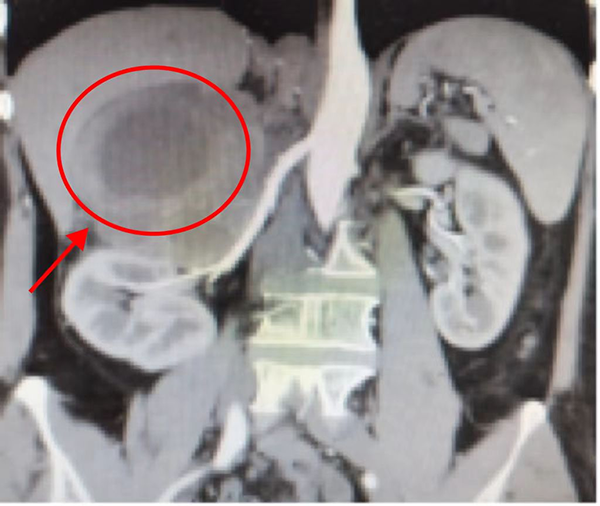

现年52岁的李女士,因为阵发右上腹部疼痛,检查发现右侧肾上腺肿物,因为肿物体积较大,当地医院建议患者前往上级医院进一步检查及治疗,患者及家属经过多方打听,最终来到了沈阳市第五人民医院。泌尿肿瘤外科的姜心主任第一时间查看了患者情况,并进行详细的病史询问、体格检查及完善必要的化验及影像学检查。结果认为患者右侧肾上腺肿物,大小约为11*10*8cm,为肾上腺原发,考虑为嗜铬细胞瘤可能性极大,但不同于一般常见的嗜铬细胞瘤,此肿瘤体积相当于一个椰子大小,属于巨大嗜铬细胞瘤,发生率极为罕见并且良恶性待定。姜心主任介绍:“嗜铬细胞瘤发作血压会突然升高,就像坐过山车那样忽高忽低、变化莫测,凶险万分。”并且肿瘤自身血供丰富,与下腔静脉及右肾动静脉关系密切,无论是开放手术还是微创手术难度及风险都极大。泌尿肿瘤外科团队进行详细的术前讨论,制定相应预案,并且请麻醉科金永涛主任进行会诊,共同为患者制定了一套完善的手术方案,确保患者围手术期的安全。术前2周予以药物准备控制血压,术前1周液体扩容。